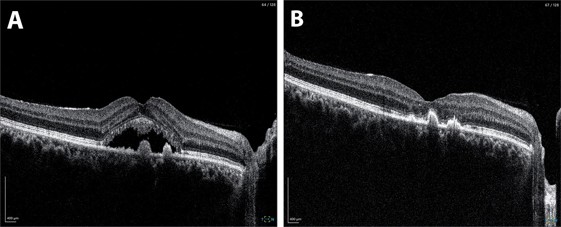

Fig 2. A. At baseline, OCT through the right fovea demonstrates subretinal fluid with small hyper-reflective pigment epithelial detachments. B. Following laser, there has been complete resolution of subretinal fluid at the fovea.

The results were notable from an anatomical standpoint. At two-month follow-up, OCT demonstrated complete resolution of subretinal fluid, while autofluorescence imaging confirmed preservation of RPE integrity at the fovea with no treatment-related damage.

However, functional outcomes were more complex. Despite excellent anatomical resolution, the patient reported minimal subjective visual improvement, with visual acuity remaining stable at 6/9. This likely reflects chronic photoreceptor changes from prolonged fluid accumulation, highlighting the importance of early intervention in CSCR.